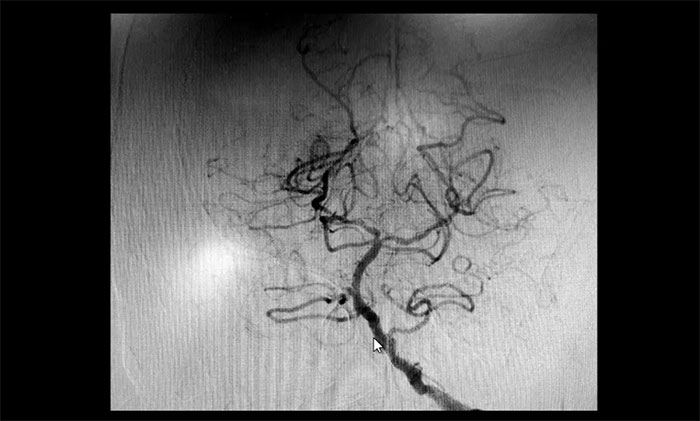

颈内动脉狭窄可分为轻度(<50%),中度(50%~69%)和重度(70%~99%),椎动脉狭窄的判别标准与之相仿。DSA检查示:患者双侧颈内动脉及左侧椎动脉存在重度狭窄,狭窄程度达到甚至超过90%,病情十分严重,遂立即收治入院。

▲ 双侧颈内动脉及左侧椎动脉重度狭窄

▲ 术后,左侧颈内动脉狭窄明显改善

术后康复观察一月余,于耀宇主任团队再次为曹老伯行右侧颈动脉支架置入及左侧椎动脉支架置入手术。术中造影显示,右侧颈内动脉起始段重度狭窄,狭窄长度8mm左右。左侧椎动脉 V4 段重度狭窄,长度6mm左右。运用娴熟扎实的技术,在充分做好脑保护的前提下经过多次球囊扩张后,顺利释放支架于狭窄处。造影提示支架打开良好,血管狭窄基本恢复正常,支架贴壁佳,支架内血流通畅,远端血流良好。

▲ 术后,右侧颈内动脉及左侧椎动脉狭窄明显改善